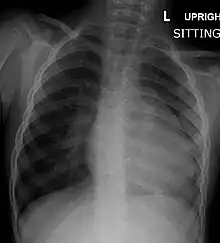

Before more sophisticated techniques became available, chest x-ray was the definitive method of diagnosis. The abnormal "coeur-en-sabot" (boot-like) appearance of a heart with tetralogy of Fallot is classically visible via chest x-ray, although most infants with tetralogy may not show this finding.[37] The boot like shape is due to the right ventricular hypertrophy present in TOF. Lung fields are often dark (absence of interstitial lung markings) due to decreased pulmonary blood flow.[15]: 171–72

| Right ventricular hypertrophy | The right ventricle is more muscular than normal, causing a characteristic boot-shaped (coeur-en-sabot) appearance as seen by chest X-ray. Due to the misarrangement of the external ventricular septum, the right ventricular wall increases in size to deal with the increased obstruction to the right outflow tract. This feature is now generally agreed to be a secondary anomaly, as the level of hypertrophy tends to increase with age.[32] |